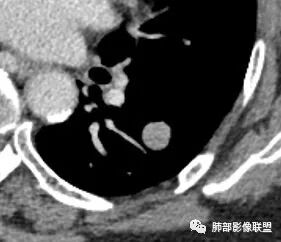

定位 左肺下叶背段斜裂旁实性小结节,边界清晰,密度尙均匀,未见脂肪钙化,与支气管关系不密切,可见肺血管贴边,增强呈轻中度强化,平扫47hu 动脉期48 静脉期67hu,

定性 常规考虑 良性结节,错构瘤或PSP可能,鉴别类癌,神经源性肿瘤,巨淋巴结增生,建议追观或穿刺活检。

CT值46H

增强67HU

动脉期弱一些,后期强化明显一些

动脉期边缘斑点状、结节状强化为主

后期趋向于均匀强化

动脉期测量区域——中央,不是强化区域

其实强化还算是中度,幅度超过20HU

支持良性

PSP可能 错构瘤待排